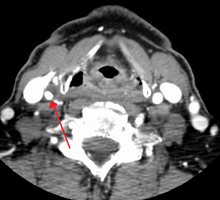

One of several different imaging modalities, such as angiogram, computed tomography angiogram (CTA)[1][2][3] or magnetic resonance imaging angiogram (MRA) may be useful. Each imaging modality has its advantages and disadvantages - Magnetic resonance angiography and CT angiography with contrast is contraindicated in patients with renal insufficiency, catheter angioigraphy has a 0.5% to 1.0% risk of stroke, MI, arterial injury or retoperitoneal bleeding. The investigation chosen will depend on the clinical question and the imaging expertise, experience and equipment available.[4]